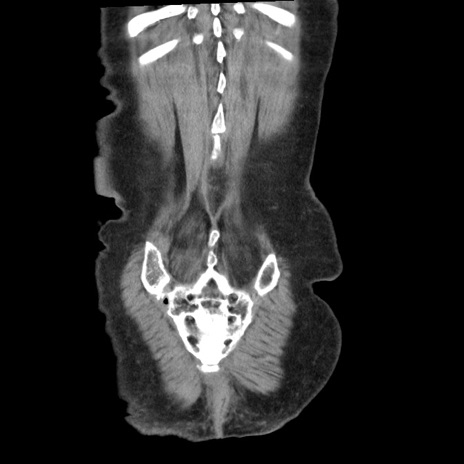

矢状断像

【症例】80歳代女性

【主訴】腹痛

【現病歴】8時間前から腹痛あり来院。

【既往歴】糖尿病、脂質異常症、子宮体癌にて子宮全摘術

【身体所見】意識清明・会話良好だが腹痛で苦悶様、全腹部にわたって反跳痛と圧痛あり

【データ】WBC 13600、CRP 0.14、LDH 224、CK 90